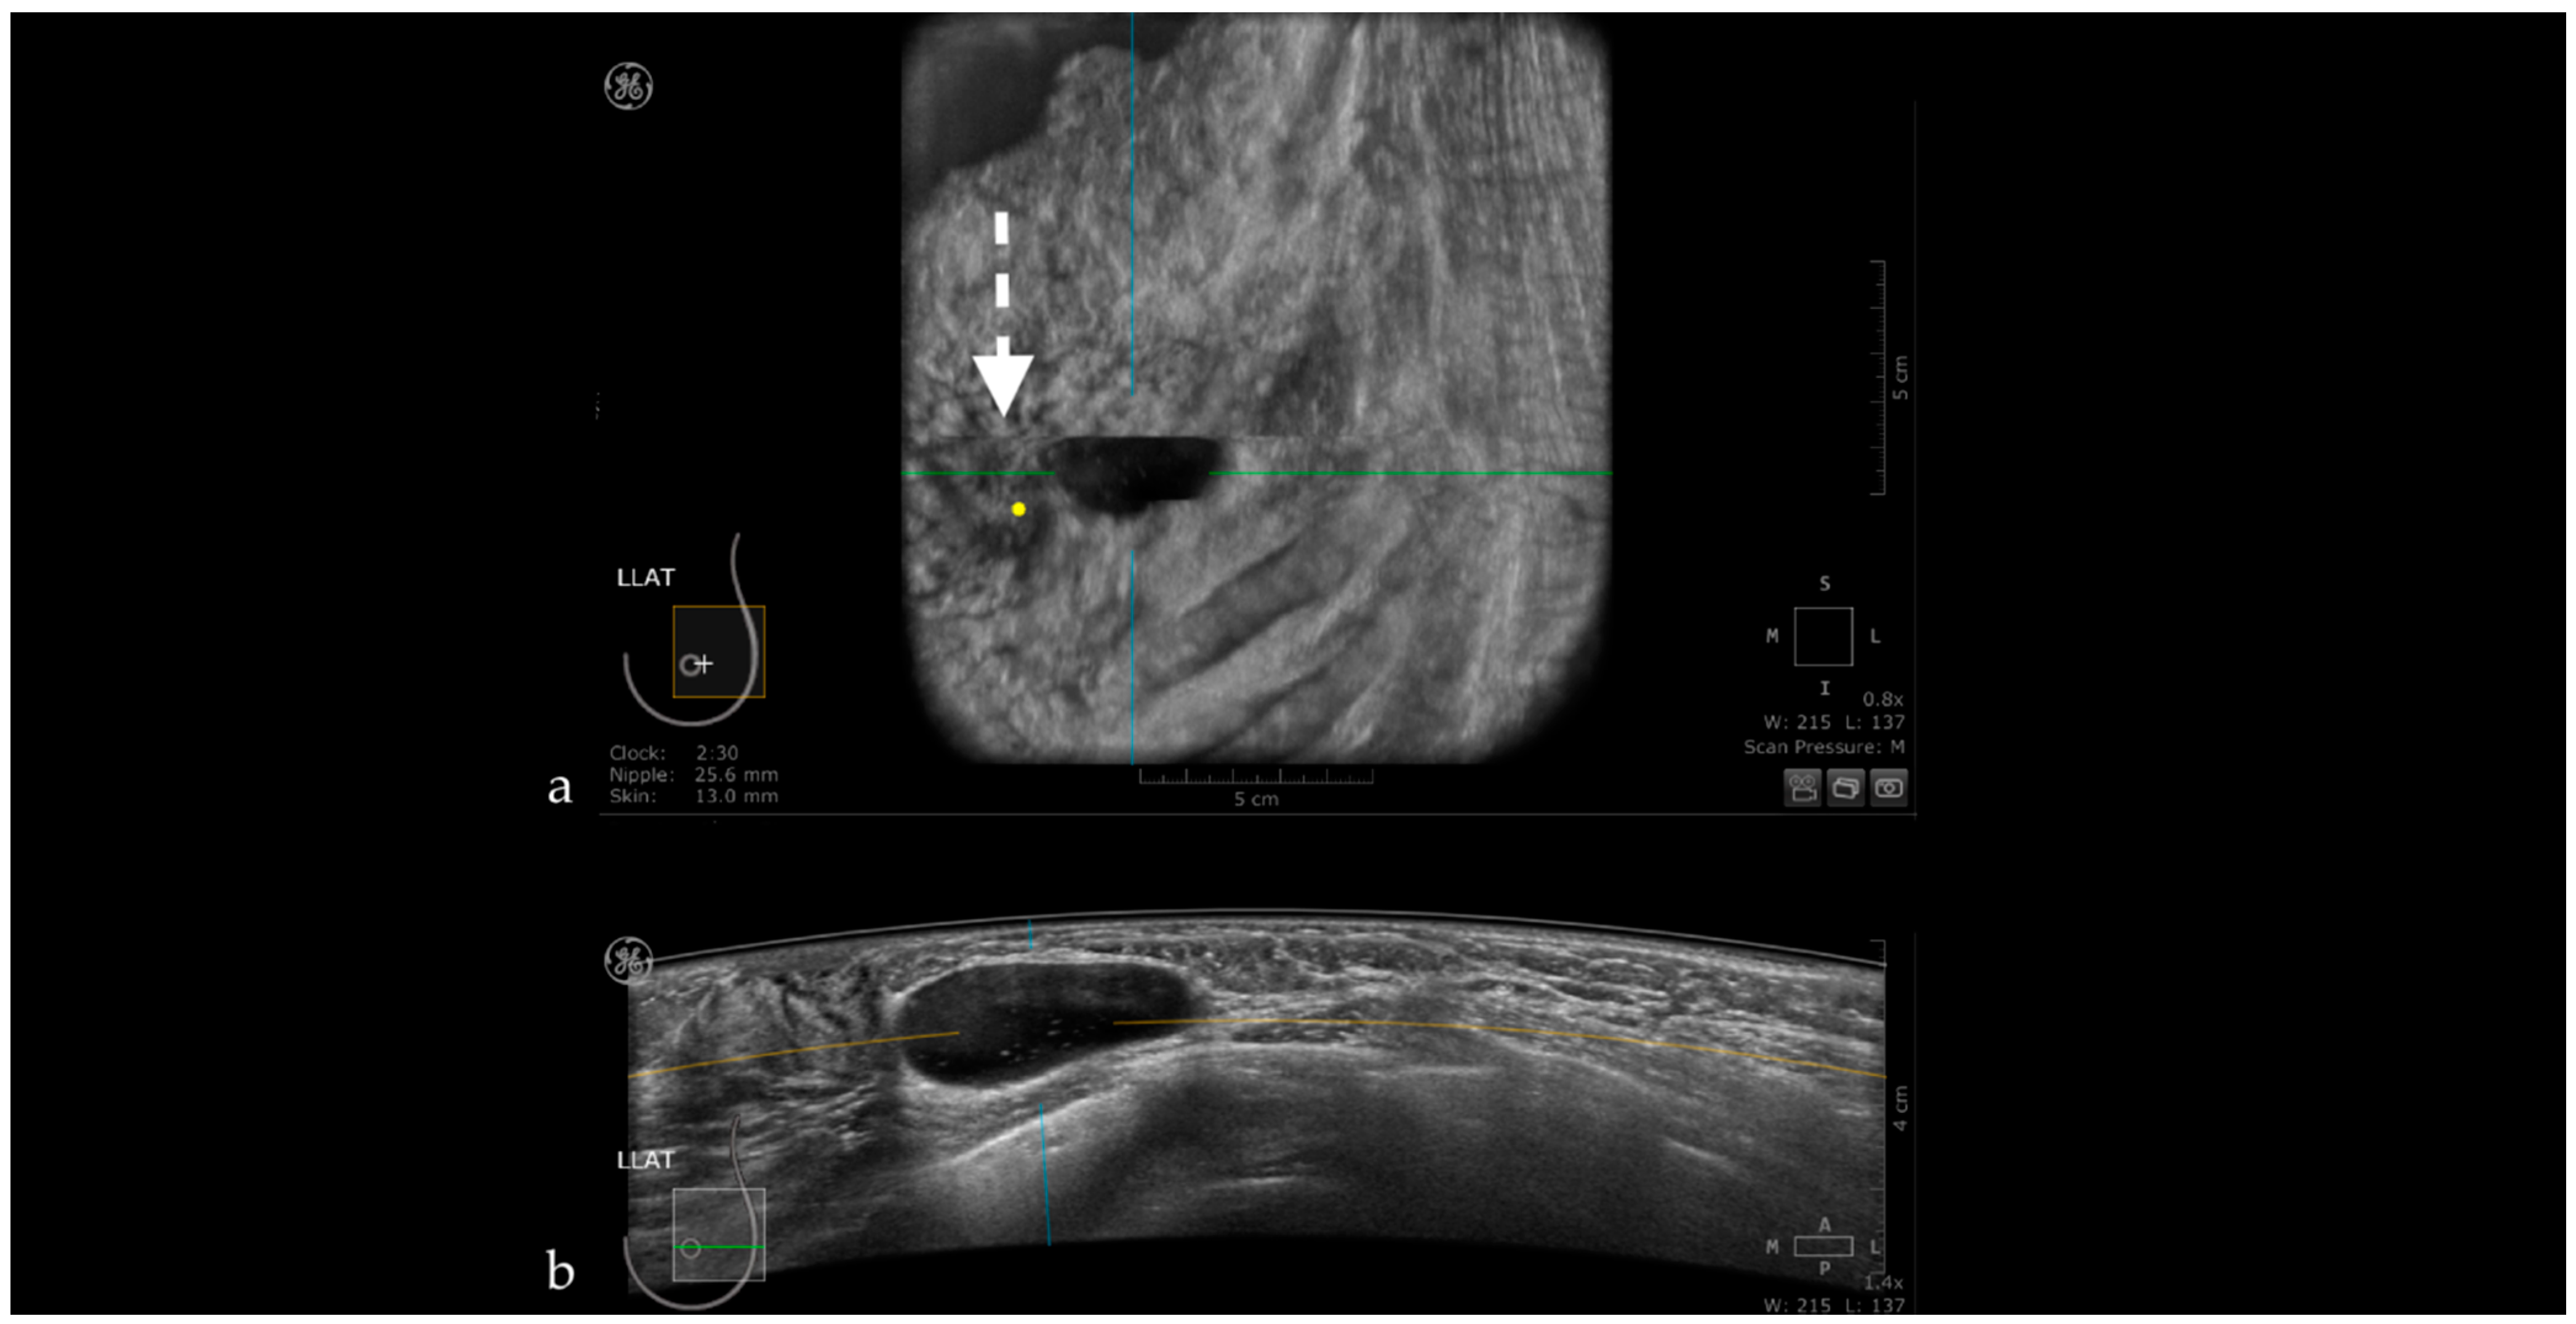

The Usefulness of the Coronal Plane

- Zheng, F.Y.; Yan, L.X.; Huang, B.J.; Xia, H.S.; Wang, X.; Lu, Q.; Li, C.X.; Wang, W.P. Comparison of retraction phenomenon and BI-RADS-US descriptors in differentiating benign and malignant breast masses using an automated breast volume scanner. Eur. J. Radiol. 2015, 84, 2123–2129. [Google Scholar] [CrossRef] [PubMed]

- Chae, E.Y.; Cha, J.H.; Kim, H.H.; Shin, H.J. Comparison of lesion detection in the transverse and coronal views on automated breast sonography. J. Ultrasound Med. 2015, 34, 125–135. [Google Scholar] [CrossRef]